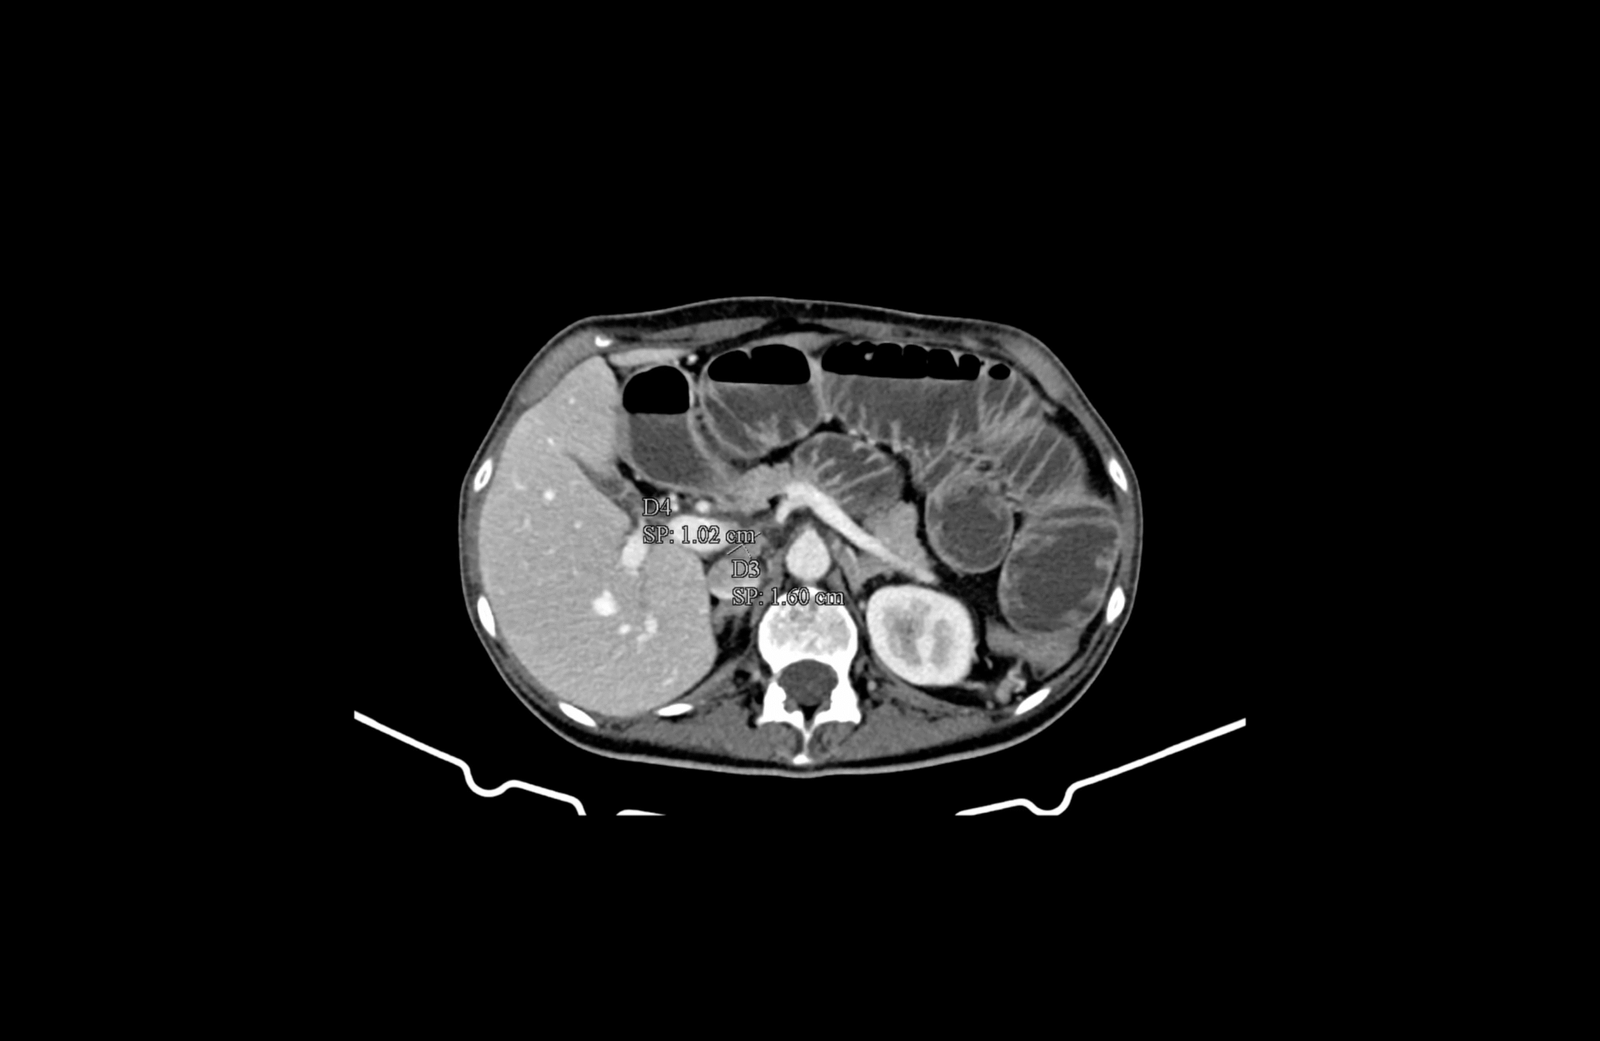

Извърши се компютърна томография на корем и малък таз, която установи:

- локално авансирала туморна формация на десния колон с огромни размери

- механичен илеус с пълен стоп в дисталния отдел на тънките черва с прераздути и оточни тънкочревни бримки, по цялата им дължина

- локорегионална метастатична лимфаденомегалия обтураторно, параилиачно, ретроперитонеално до нивото на бъбречните съдове

- инфилтрация на мастната бъбречна капсула в дясно

- инфилтрация на предната коремна стена

- инфилтрация на m. psoas major и n. femoralis

- инфилтрация на m. iliacus, граничеща с илиачната кост

- ангажиране на вътрешната илиачна съдова дъга

- инфилтрация на тънкочревни бримки от дисталния илеум по съседство

- не се откриха паренхимни метастази

Авансирала туморна формация на десния колон, на фона на силно раздути тънкочревни бримки, в условията на механичен илеус

Медиална компресия и деформиране на лумените на десните общи и външни илиачни съдове. Прорастване на тумора през цялата дебелина на m. iliacus

Инфилтрация на меките тъкани на предната коремна стена

Инфилтрация на меките тъкани на предната коремна стена и m. iliopsoas, както и прилежащия към него n. femoralis

Параилиачна лимфаденомегалия с размер на възлите до 2см.

Ретроперитонеална лимфаденомегалия, суспектна за малигнена.